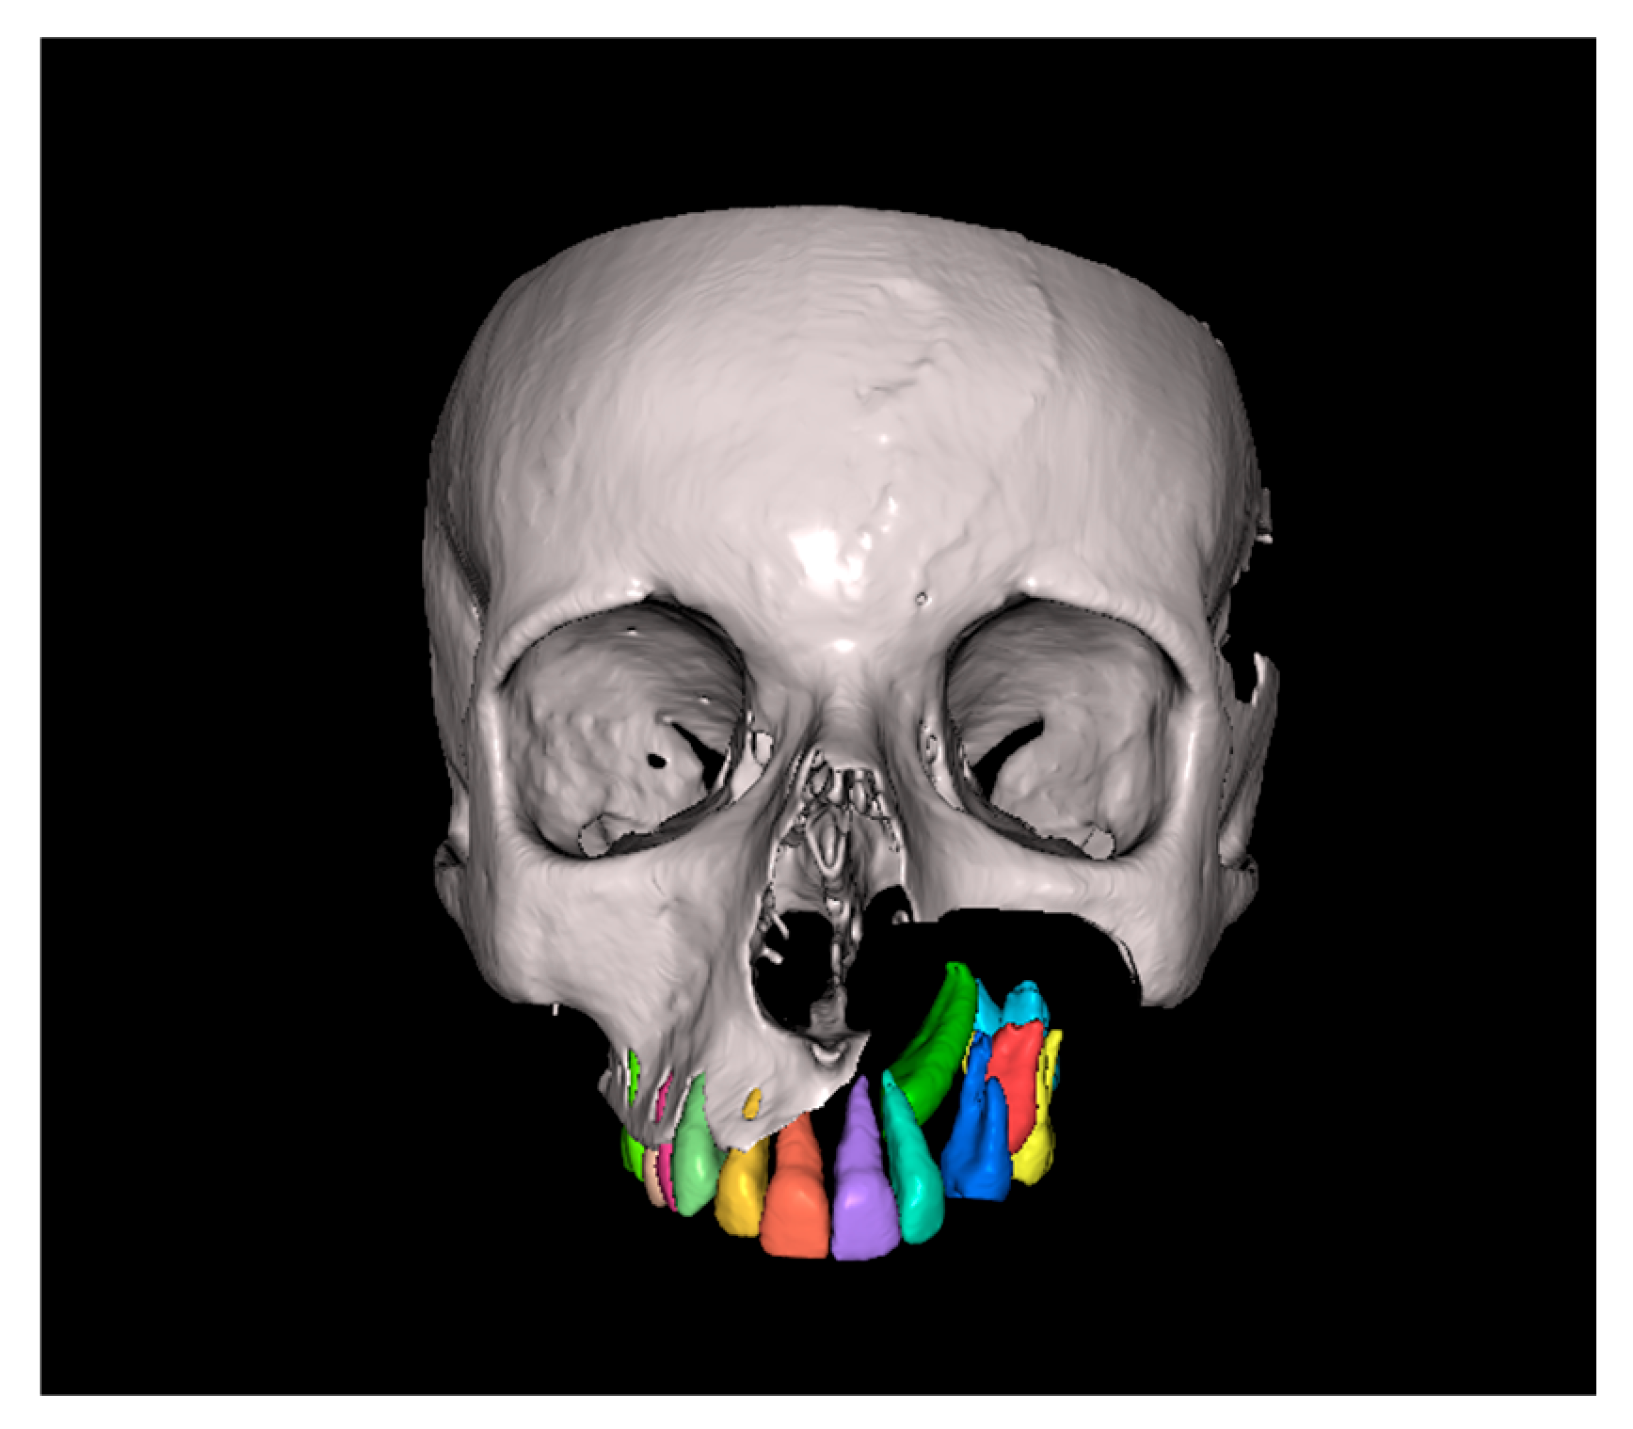

Since the IC is not visible in the initial STL, it was necessary to know its three-dimensional location. As performed in the other method, the initial CBCT scan (Figure 2) was opened in the program, and all teeth were segmented. Although Figure 2 shows the skull model, only the teeth segmentation is necessary for this method. A small cut was made to allow visualization of the IC (Figure 3).

Figure 2.

Initial CBCT scan.

Figure 3.

Initial CBCT after tooth segmentation.